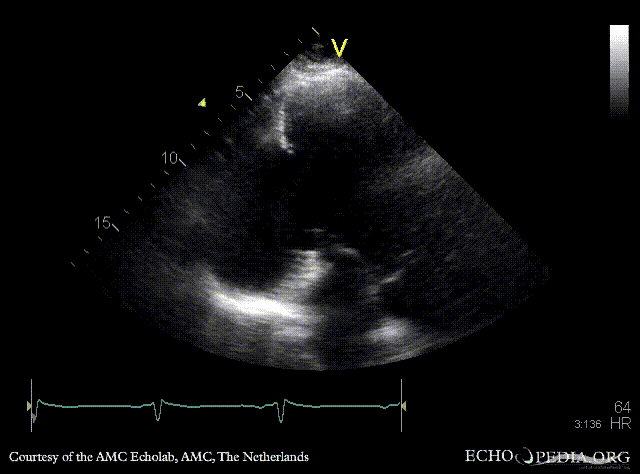

PLAX: large pseudoaneurysm of posterior wall PLAX: Color Doppler, severe mitral regurgitation